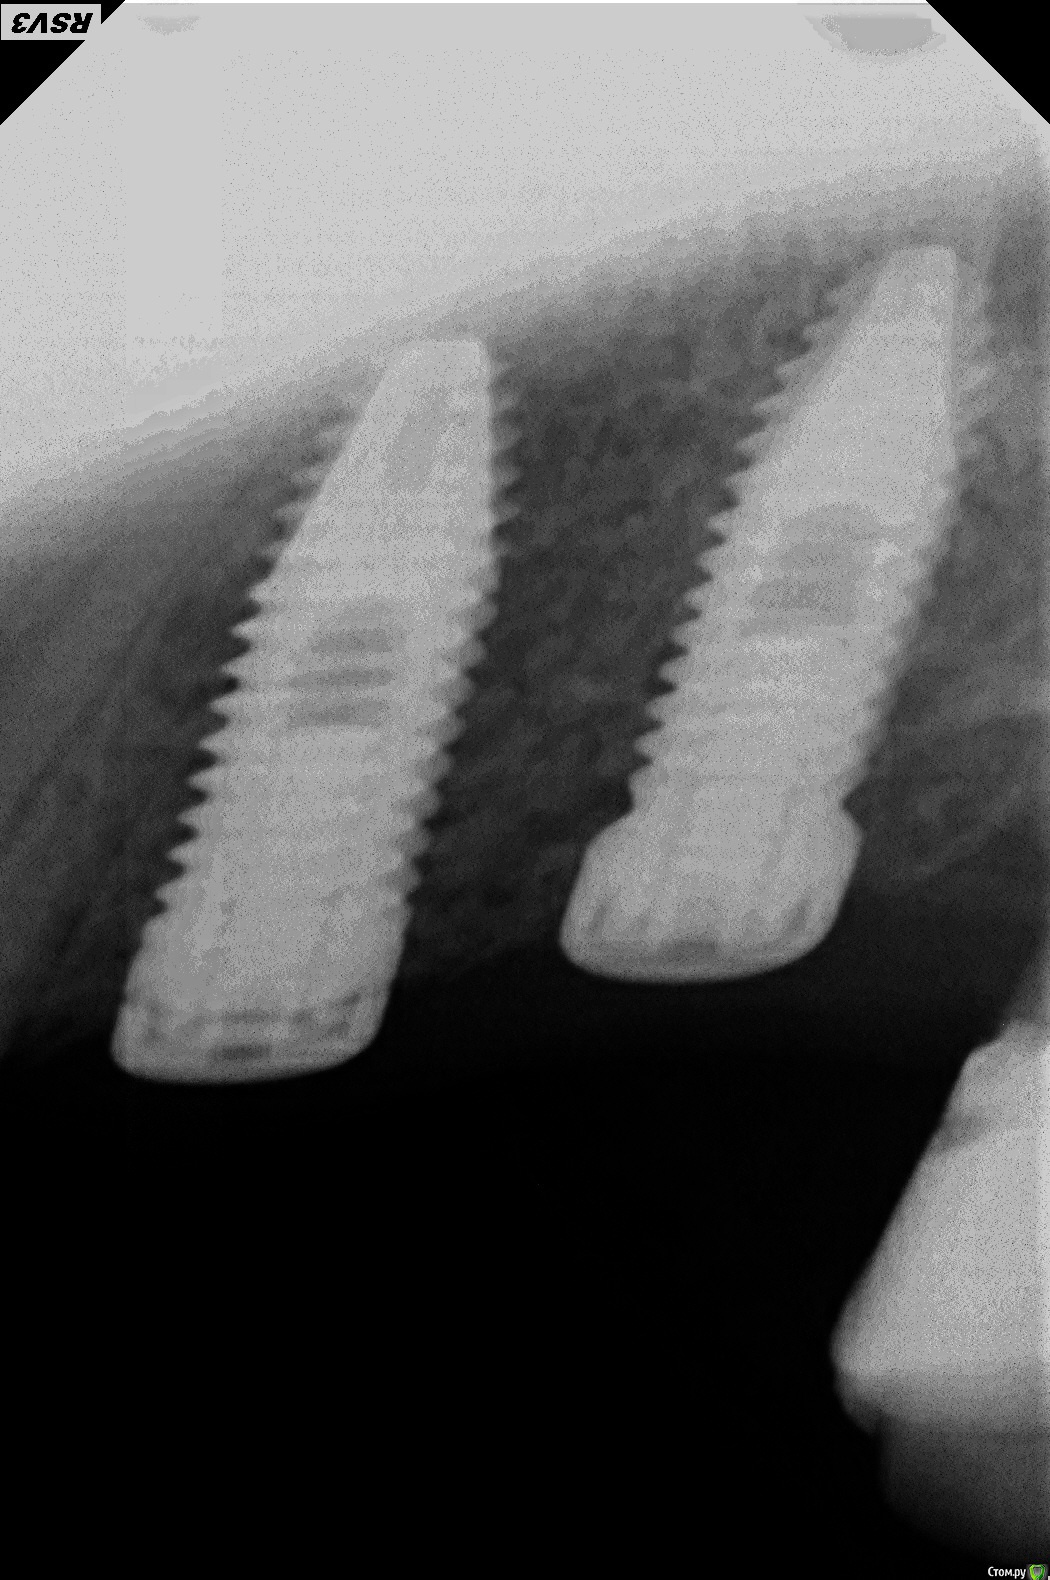

Vadsand Опубликовано 27 июня, 2016 Поделиться Опубликовано 27 июня, 2016 Коллеги подскажите какая фирма имплантатов? Пациент заимплантирован в Португалии, а чем никто не сказал, связи с докторами тамошними нет.... Ссылка на комментарий